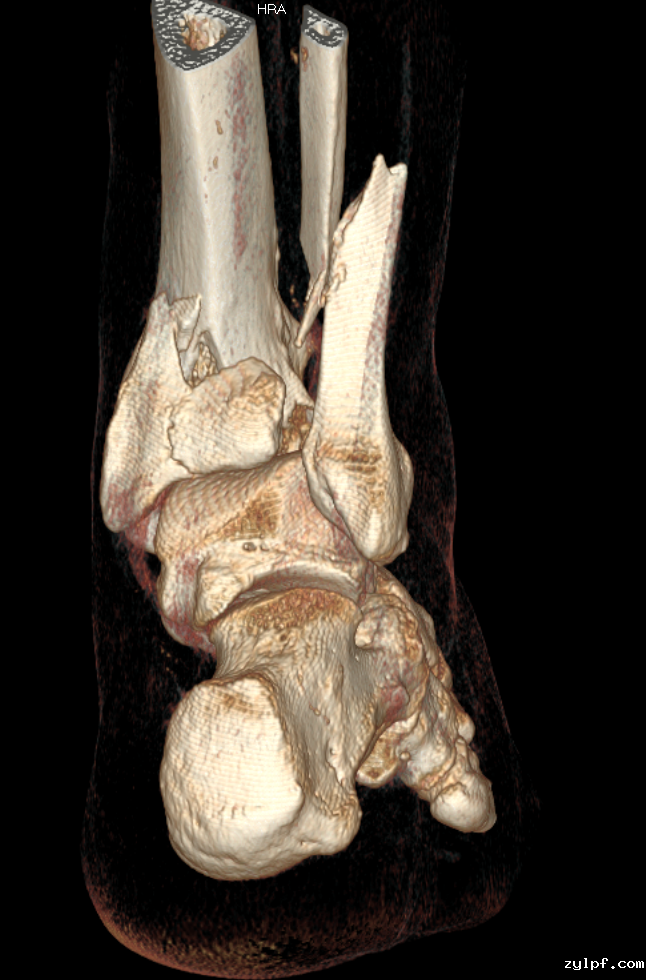

经CT扫描表明患者右胫腓骨远端粉碎性骨折(旋后-外旋型)合并右踝关节后脱位及右侧下胫腓联合损伤。

三踝骨折合并后脱位